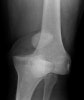

X-ray : 슬관절 탈구(Knee dislocation)

슬관절 탈구(Knee dislocation) : 매우 강한 외상으로 슬관절 전체가 빠졌어요

대부분은 Femur에 대한 Tibia의 전방전위입니다.